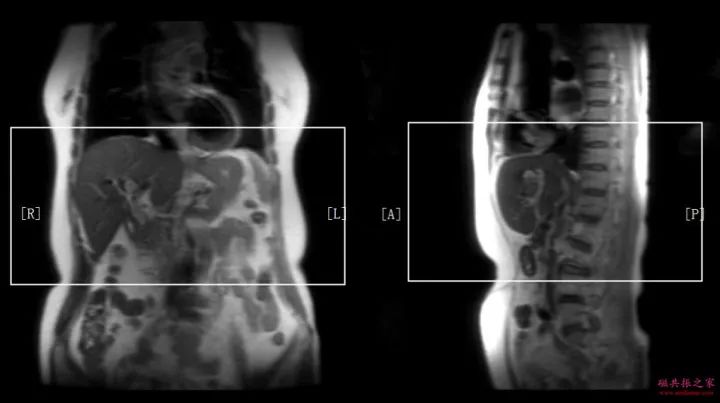

冠状面:冠状面稳态自由进动序列/单次激发T2WI序列。

在横轴位和矢状位定位,扫描范围包括肝脏前后缘,合理调整扫描范围,需包括整个病变范围。

上腹部的扫描应首先扫描范围较大的冠状面图像,以便对病变及周围组织器官作出大体地评估,更有利于精准地定位和扫描方案的制定。

冠状位:冠状位平衡期/延迟期增强补充序列

在横轴位及矢状位上定位,范围包括整个肝脏及病变范围。

大范围的冠状位增强序列有助于对血管、胆管、十二指肠区域以及周围受累情况的评估,